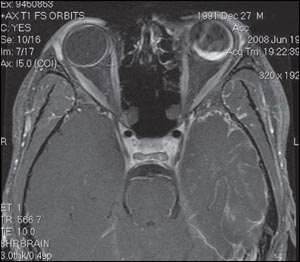

Ultrasonogram of the orbit revealed choroidal hemorrhage in the left orbit with overlying retinal detachment. Patient's MRI scan is shown.

The MRI scan confirmed the ultrasonographic findings and also showed atrophy of the cortex on the left side with prominent overlying venous malformation. A diagnosis of Sturge-Weber syndrome was made on the basis of the patient's clinical appearance and radiological findings.